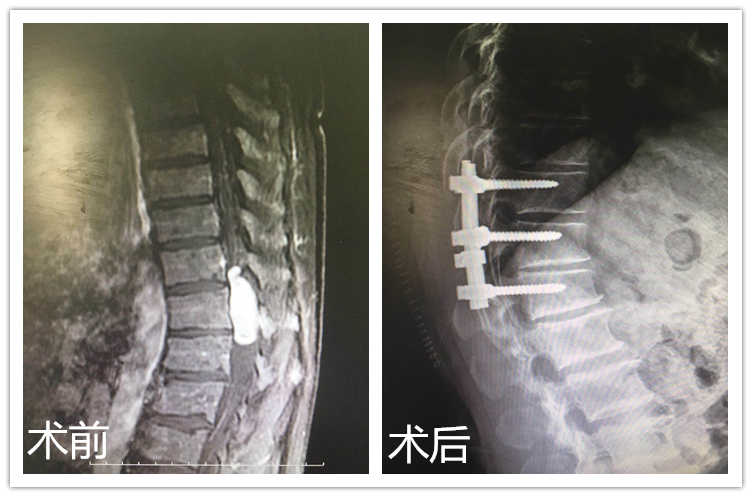

近日,我院骨三科成功开展了一例胸椎管内肿瘤切除术。该患者肿瘤位于胸11-腰1椎管内,严重压迫脊髓,手术难度、风险较大。

患者张某,男性,60岁,胸腰椎及双下肢疼痛、麻木,渐进性行走困难4年,双下肢不全瘫、大小便失禁1个月,坐轮椅来入我院。经核磁显示胸11-腰1椎管肿瘤,经骨三科专家讨论,必须及时实施手术切除肿瘤,以减轻或缓解肿瘤对脊髓神经的压迫和损害。然而,成功总是伴随着风险,手术难度也显而易见:肿瘤组织与脊髓附着一处,手术入路复杂、出血多,若显露不充分,肿瘤可能无法完整切除,手术创伤致脊髓神经二次受损,严重者会造成患者终身截瘫。但目前手术切除是治疗椎管内肿瘤较为积极有效的方法,经过严密的分析和判断之后,骨三科的专家们成竹在胸:凭借现有的经验和技术,这些困难都是可以克服和避免的。随之,一套完善的手术方案也应运而生。

手术由骨三科兰荫梧主任主刀,主治医师杜鹏协助,历时3个小时,术中患者生命体征平稳,肿瘤完整切除。经过几天的恢复,目前患者脊髓神经功能恢复良好,四肢活动自如,状态逐渐转好,笼罩在患者脸上的阴霾也被笑容所取代。患者张某感慨,是兰主任和杜大夫给了我第二次生命,骨三科的医护人员不仅专业技术过硬,更是仁心仁德,为患者解除病痛,带来生命的阳光与希望。